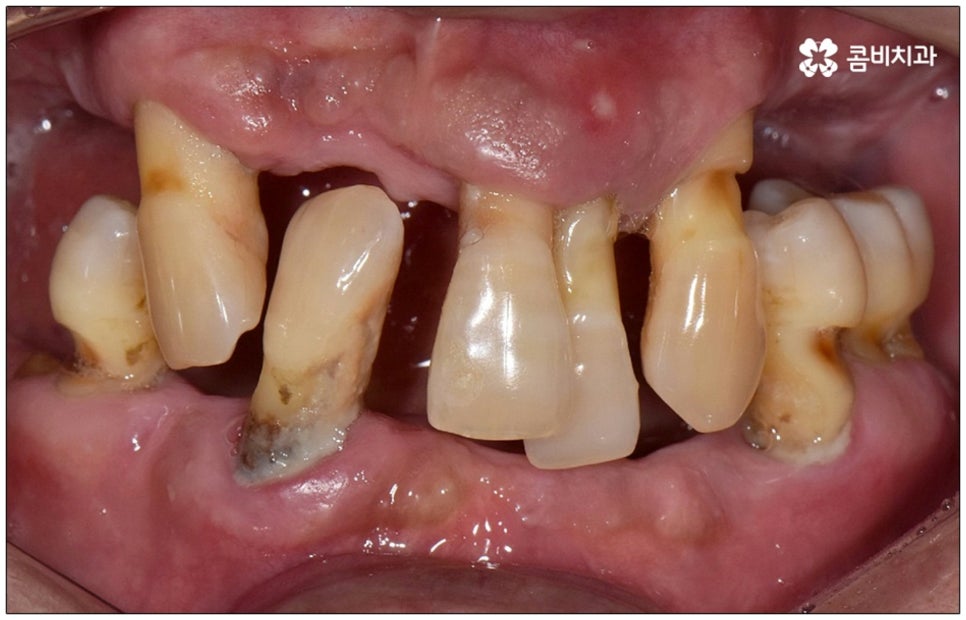

성인 이후 치아 상실의 주된 원인은 바로 풍치인데요, 풍치 즉 치주 질환은 잇몸(치은)을 포함한 치아 주위 조직에 급성 또는 만성으로 염증이 생겨서 손상이 일어난 것을 의미하고 있습니다. 이러한 풍치의 주된 원인은 치태와 치석으로, 음식물 찌꺼기와 치아 표면의 세균막(치태=플라그)이 엉겨붙어 굳어진 치석은 평상시의 칫솔질로는 제거되지 않기 때문에 스케일링 치료를 통해 주기적으로 제거해 줄 필요가 있어요. 치석이 점점 쌓이면 세균이 급증하는 온상이 되어 주변 조직에 염증이 발생하기 쉽고 병증이 심해질수록 치주인대와 치조골까지 손상이 깊어져 결국 치아가 빠지게 되는 거예요. 풍치로 치아를 잃게 되면 임플란트를 심는데도 어려움이 있기 때문에 이렇게 상황이 나빠지기 전에 제 때 적합한 치료를 받을 필요가 있어요. 하지만 잇몸의 경우 병증이 많이 깊어질 때까지 잘 알아차리기 힘든 경우가 많으므로 정기 검진 및 스케일링과 같은 평상시의 관리가 중요하다는 말씀을 드린 거예요.

특히 다수의 치아를 상실했을 때 전체적인 교합, 골조직 및 잇몸 상태, 얼굴형과의 조화 등 모든 부분을 종합적으로 고려하여야 하며 노인임플란트 수술의 경우 다양한 변수가 발생할 수 있기 때문에 이러한 고난도 임플란트 케이스에 노련하게 대처할 수 있도록 풍부한 임상 경험과 노하우를 갖춘 의료진인지, 정밀 검진 기계를 보유하고 있는지, 처음부터 끝까지 철저한 케어 시스템을 갖추고 사후 관리까지 꼼꼼하게 진행하는지 등을 잘 살펴보시고 임플란트 수술을 진행할 치과를 신중하게 선택하시길 권유드리고 있습니다.

2025년이 되면 한국의 고령 인구 비중이 20.6% 로 초고령 사회에 진입할 것으로 보여진다고 하는데요, 자연 치아를 보다 오랜 기간 동안 건강하게 사용할 수 있기 위해서 젊었을 때부터 관리를 꾸준하게 해 주는 것도 중요하지만 혹시라도 치아의 일부 또는 전체를 상실하게 되었을 때 이를 수복하기 위한 방법에 대해서도 잘 알아두고 시기를 놓치지 말고 바로 임플란트 수술 등을 진행하는 것 또한 중요한 부분일 거예요.